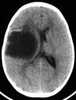

Desmoplastic infantile ganglioglioma